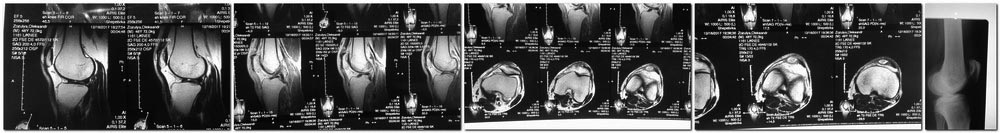

1. По одному заключению мрт нельзя диагностировать остеомиелит надколенника.

2. Беря во внимание клинику - отёк и гиперемия в области бугристости большеберцовый кости, при пункции получен гной, а так же механизм травмы (работа на коленях), можно думать о хроническом гнойном бурсите области бугристости большеберцовой кости с вовлечением в гнойный процесс собственной связки надколенника.

Вот фотографии коленного сустава.

Выражена гипотрофия четырехглавой мышцы